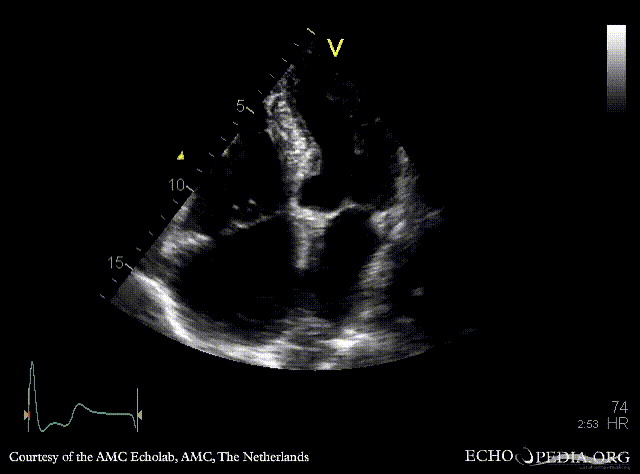

| PSAX: stenosis of aortic valve | PLAX with Color Doppler: high velocity transaortic flow, mild aortic regurgitation |